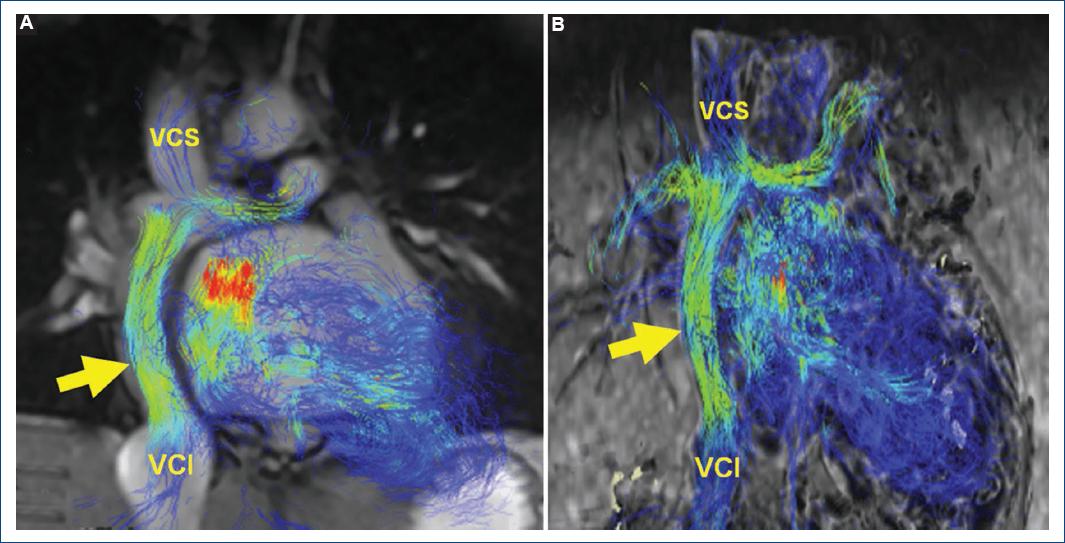

En este caso se realizó una reconstrucción en secuencia de flujo 4D coronal fusionada de la conexión cavopulmonar total y en secuencia de flujo 4D en respiración libre (Fig. 3), cubriendo el área de interés entre el túnel de Fontan (por encima de la entrada de las venas hepáticas), la vena cava superior (por debajo de la vena braquiocefálica) y las arterias pulmonares derecha e izquierda hasta los niveles de las ramas segmentarias, permitiéndonos evaluar la permeabilidad del tubo de Fontan y calcular el Qp/Qs (Fig. 4), donde se determinó la permeabilidad del mismo y la ausencia de circulación colateral aortopulmonar.

Figura 3 Ejemplo 2: paciente de 14 años con diagnóstico de atresia tricuspídea con cirugía de Fontan, enviado a resonancia magnética cardiaca (RMC) para análisis de la permeabilidad del mismo y valoración de colaterales. A: RMC en secuencia de flujo 4D con análisis de líneas de corriente y cine del conducto. B: RMC en secuencia de flujo 4D con análisis de líneas de corriente aisladas. La flecha señala un tubo extracardiaco. VCI: vena cava inferior; VCS: vena cava superior.

Figura 4 A: resonancia magnética cardiaca en secuencia de flujo 4D con líneas de corriente. B: tabla de cuantificación Qp/Qs para valorar la presencia de colaterales. VCI: vena cava inferior; VCS: vena cava superior; VPID: vena pulmonar inferior derecha; VPII: vena pulmonar inferior izquierda; VPSD: vena pulmonar superior derecha; VPSI: vena pulmonar superior izquierda.